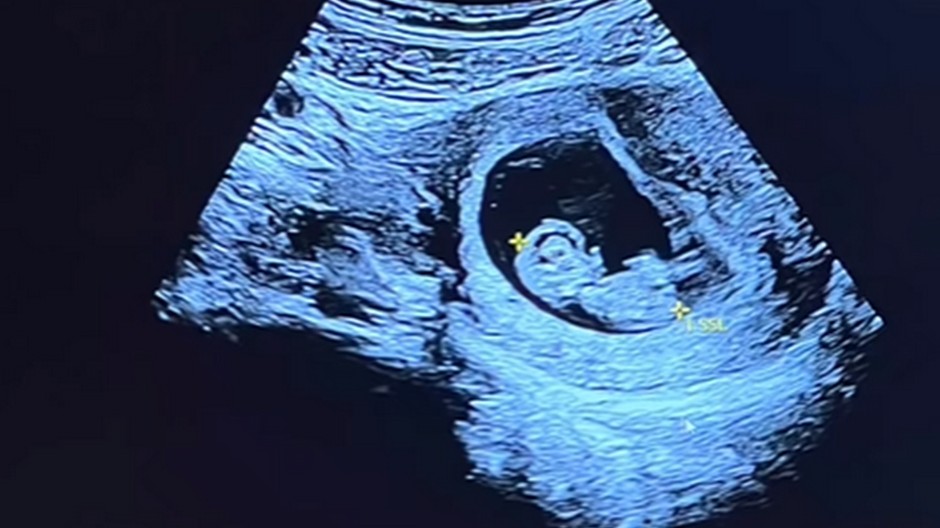

Ultrazvuk

Zdroj: INST/tamara_tippler

Človek mieni, pánboh mení. Elitná lyžiarka oznámila na Instagrame tú najkrajšiu novinu. Od milovaného športu si bude musieť dať na istý čas pauzu a ktovie - možno aj navždy. Rakúšanka Tamara Tippler je tehotná.

Rakúska lyžiarka Tamara Tipplerová predčasne ukončila sezónu a nepredstaví sa vo finále Svetového pohára v Soldeu v Andorre. Tridsaťjedenročná pretekárka oznámila, že sa stane mamičkou.